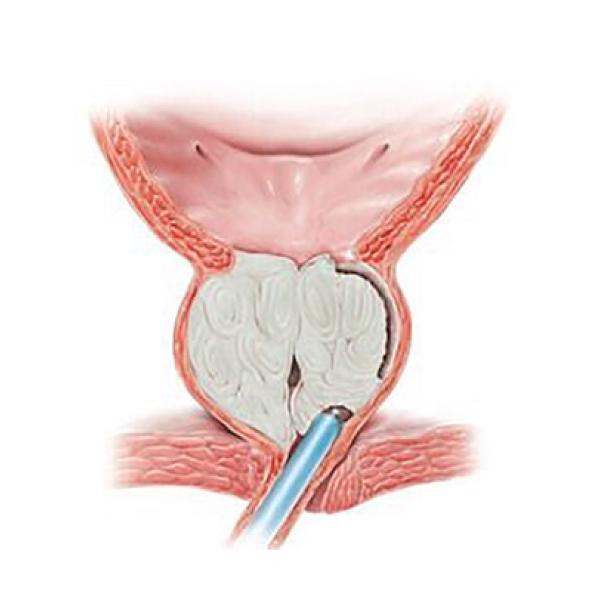

В данном случае предпочтительным является резекция единственной правой почки. Количество осложнений, которые могут сопутствовать любому хирургическому вмешательству зависят от многих параметров: опыта врача и количество выполненных подобных операций, технического оснащения и т.п.

Опухоль располагается в верхнем сегменте (полюсе) почки поэтому резекция почки имеет свои особенности, но ни в коем случае не должна обуславливать пассивную выжидательную тактику. Если у Вас остаются сомнения, проконсультируйтесь у нас очно для возможности выполнения резекции почки на базе в Москве.

В данном случае предпочтительным является резекция единственной правой почки. Количество осложнений, которые могут сопутствовать любому хирургическому вмешательству зависят от многих параметров: опыта врача и количество выполненных подобных операций, технического оснащения и т.п.

Опухоль располагается в верхнем сегменте (полюсе) почки поэтому резекция почки имеет свои особенности, но ни в коем случае не должна обуславливать пассивную выжидательную тактику. Если у Вас остаются сомнения, проконсультируйтесь у нас очно для возможности выполнения резекции почки на базе в Москве.